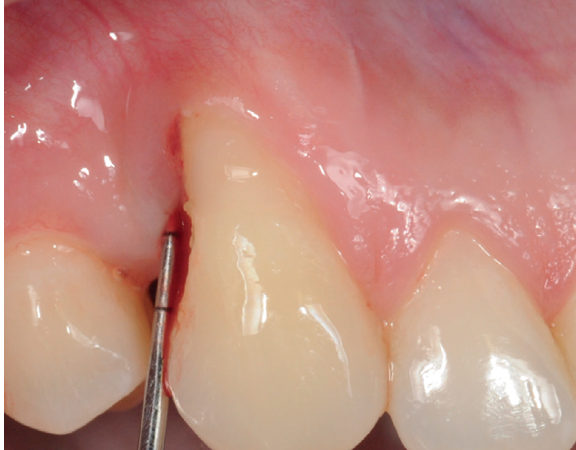

A hipersensibilidade dentinária pode ser mensurada com escalas e tratada em protocolo de sessão única. Veja mais.